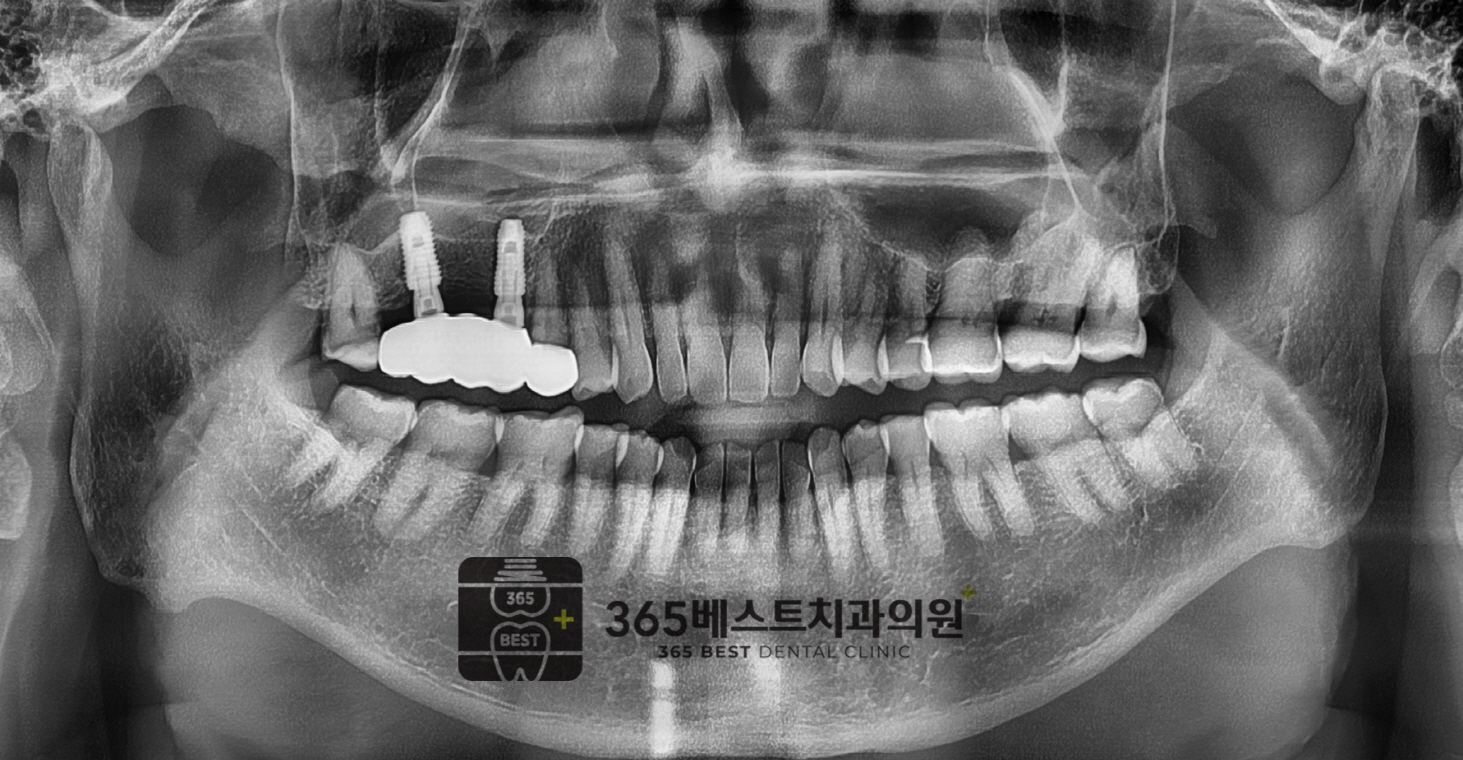

[임플란트]골재건

상악-구치부-2개-발치 후 골재건, 62세 남성

(전)